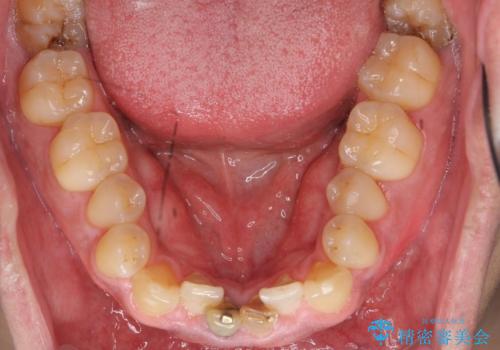

- 下の前歯の色が気になることを主訴に来院された患者様です。

下の前歯は金属の土台により黒くなり、隣の歯も神経が死んで暗く変色していました。

※右下1の再根管治療もおすすめしましたがご希望されませんでした。

※下顎前歯部の叢生について矯正も提案致しましたが、ご希望されませんでした。